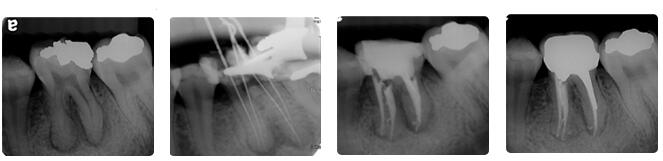

根管治疗通常包括三个基本步骤:根管预备、根管消毒、根管充填。

首先会清除根管内的炎症牙髓和坏死物质,接下来测量根管长度,并适当扩大根管(即根管预备过程),然后在根管内封药消毒,最后用药物充填根管。

根管治疗时,拍牙片是很有必要的,并且至少要保障3张牙片。

第一张在治疗前,帮助医生了解牙根的基本情况,制定治疗计划;

第二张在治疗中,帮助医生了解治疗情况,如根管预备是否到位等,并制定下一步治疗方案;

第三张是在治疗结束后,帮助判定根管充填质量,发现问题及时补救。